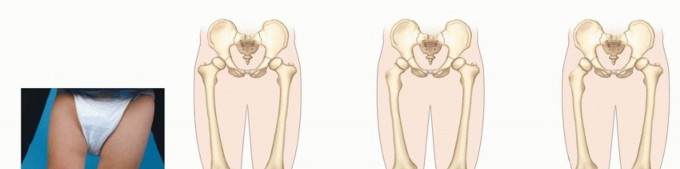

Femoral Rotational Osteotomy (Proximal and Distal) DEFINITIONS Femoral anteversion is the angle in the transv…